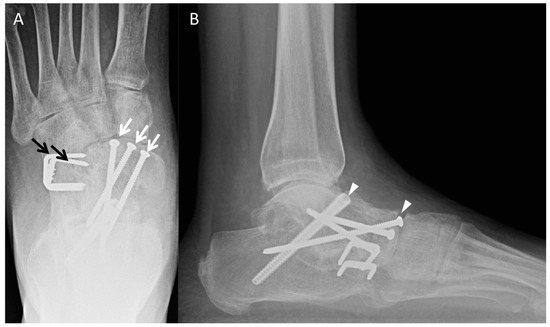

3.2. Subtalar

3.3. Triple Arthrodesis